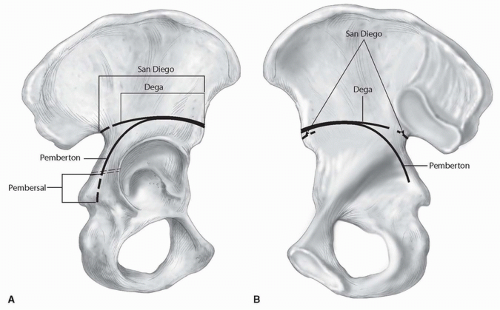

가장 흔하게 사용되는 reconstructive osteotomy 를 보게 되면 다음과 같습니다. reconstructive procedure 는 congruent joint (교합성 관절)에서만 시행할 수 있습니다.

수술자의 선호가 있는 치료가 있지만 Internal Fixation이 필요없고 예후가 괜찮고 수술법이 나쁘지않아 현재 Pemberton 이나 Dega osteotomy를 많이 사용하는 편입니다.

1. Salter 는 Acetabular index 가 10~15도 이하로 변형이 심하지 않을 때 사용할 수 있습니다. symphysis pubis를 hinge로 하여(chiari osteotomy와 hinge가 같습니다.) anterolateral을 덮어줄 수 있습니다. 단순하게 방향을 교정해주기 때문에 비구의 변형이 있는 경우 잘 사용하지 않습니다.

2. Pemberton의 경우 15도 이상의 변형에서 사용하게되며, 작은 골두와 큰 acetabulum 일때 시행하면 좋습니다. 비구의 변형을 교정할 수 있는 술식입니다. 삼방연골을 hinge로 사용하게 됩니다.

3. Dega는 pemberton에 비해 incomplete 하게 transiliac osteotomy를 시행하게 됩니다.

Pemberton이나 Dega는 volumn을 감소시킵니다.